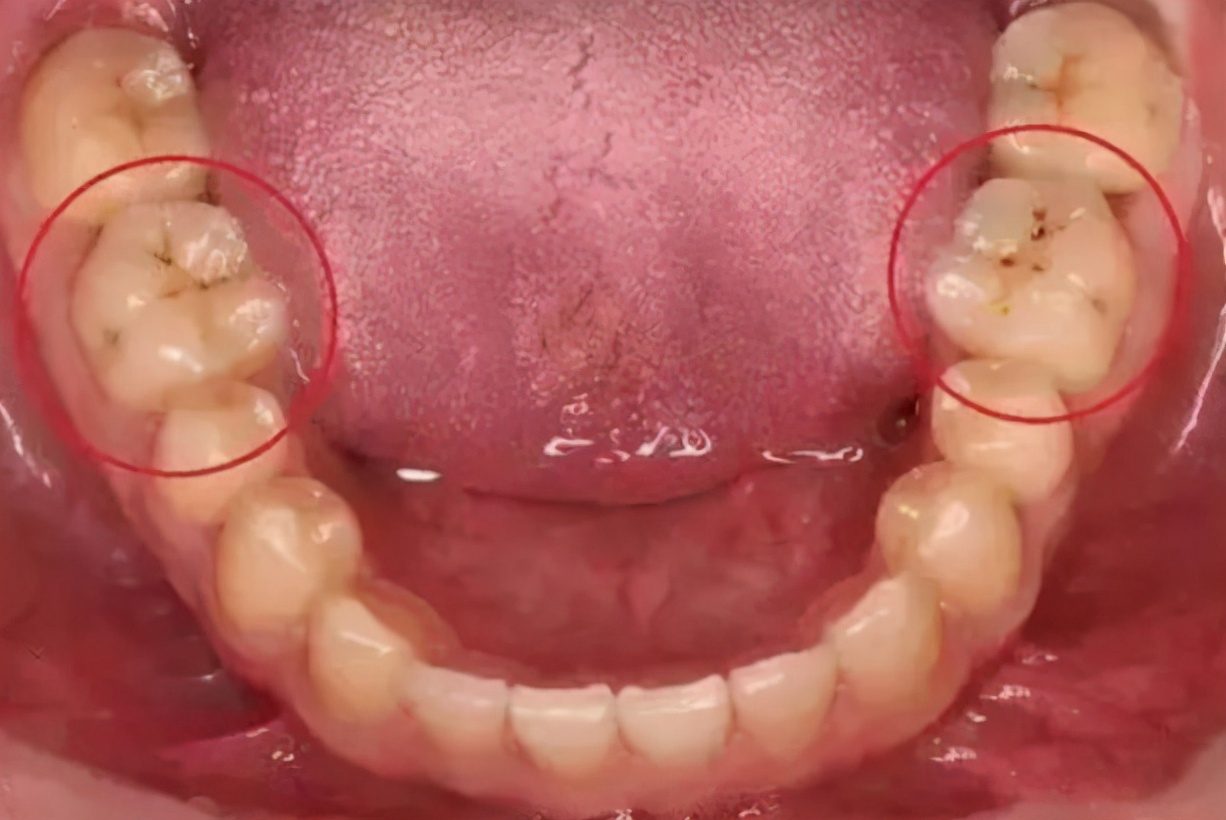

首先我们要正确地认识这个小黑点,究竟是什么原因导致的!一般来说,我们的牙齿出现小黑点,多是这两种情况:

1、色素沉着

如烟渍、茶渍、咖啡渍等。有喝茶或咖啡习惯的朋友应该能体会到,就算多么勤奋刷牙,残留在上面的茶渍、咖啡渍等是很难刷掉的。所以这时候,需要通过洗牙来去除!

2、蛀牙

另一种可能是,发生了蛀牙!从表面看是表现为一个黑点,如果这样的情况不及时干预,会由小黑点进而形成龋洞,形成蛀牙,这是一个慢性的过程,通常需要1.5-2年。

所以,发现后尽早地去处理是可以及时控制不让情况加重的;另外每半年或一年做一次口腔检查,也是可以及早发现问题及早治疗。

出现小黑点,要及时去医院检查,由专业的医生去判断是色素沉着还是蛀牙!